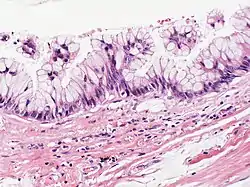

Mucinous cystadenocarcinoma

| Atypical goblet cells with focal tufting. The classification of these rare neoplasms is difficult and controversial. There appears to be a spectrum of mucinous cystic tumors ranging from those that are obviously benign (benign epithelium and no tumor invasion into surrounding lung) to those that exhibit invasion into surrounding lung tissue and are, therefore, malignant. In between is a group of neoplasms that exhibit epithelial atypia but no tumor invasion into lung tissue and the malignant potential of these is uncertain. This case appears to fall into that category. Focal cyst rupture with extravasation of mucin into surrounding lung tissue may occur with all types of mucinous cystic tumors. | |

It can occur in the breast[1] as well as in the ovary.[2] Tumors are normally multilocular with various smooth, thin walled cysts. Within the cysts is found a haemorrhagic or cellular debris.[2]